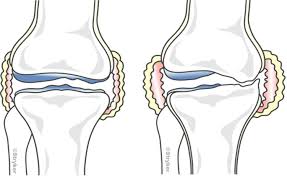

무릎 인공관절 수술, 왜 필요한가요?

무릎관절은 체중을 가장 많이 지탱하는 관절입니다. 나이가 들수록 연골은 점차 마모되고, 충격을 흡수하는 능력도 감소합니다. 이로 인해 통증, 뻣뻣함, 운동 제한이 생기며, 이런 증상이 악화되면 인공관절 수술이 필요해집니다.

퇴행성 관절염 외에도 류마티스 관절염이나 외상 후 관절 손상이 심각할 경우 수술이 권유되며, 수술을 통해 환자는 통증 없이 보행이 가능해지고 일상생활로 복귀할 수 있게 됩니다.